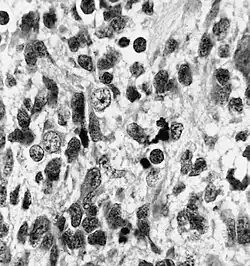

Histopathology of medulloepithelioma showing characteristic neural tube like strands.

Histologically, medulloepithelioma resemble a primitive neural tube and with neuronal, glial and mesenchymal elements.[8][9] Flexner-Wintersteiner rosettes may also be observed.[10]

Immunohistochemically, neural tube-like structures are vimentin positive in the majority of medulloepitheliomas.[11] Poorly differentiated medulloepitheliomas are vimentin negative.